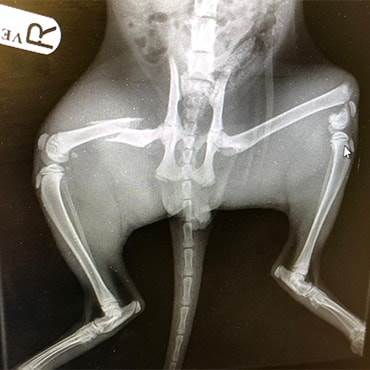

After calling Sarah took Buddy to our Huyton PDSA Pet Hospital in Liverpool where our emergency veterinary team began urgent treatment to save his life. After being stabilised and given pain relief, X-rays revealed he had broken both of his hind legs. His chances of survival were looking extremely slim due to both the severity of the breaks and the risk of anaesthetic for a kitten in need of such complex surgery.

In a bid to save his life, the team began the intricate three hour operation to pin the broken bones in his tiny legs back together.